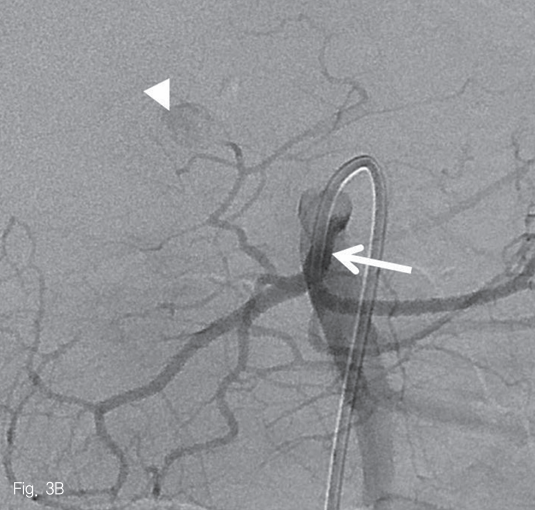

우측 대퇴동맥을 천자하여 5-Fr sheath(Radifocus; Terumo, Tokyo, Japan)를 삽입한 뒤, 5-Fr Cobra catheter(Cook Medical Inc, Bloomington, USA)를 사용하여 상장간막동맥 조영술을 시행하였다. 중간결장동맥의 근위부에 조영제가 채워지는 낭모양의 가성동맥류가 보였다 (Fig. 3A). 중간결장동맥은 상장간막동맥에서 후방으로 기시하여 5-Fr catheter로 선택하기 어려웠다. 0.035-in shapeable guidewire(Radifocus; Terumo, Tokyo, Japan)를 이용하여 중간결장동맥의 근위부까지 5-Fr catheter로 진입하였다 (Fig. 3B). 2.0-Fr microcatheter (Progreat; Terumo, Tokyo, Japan)를 이용해서 병변 직전까지 초선택하였다 (Fig. 3C). N-butyl-2-cyanoacrylate (Histocryl; B. Braun, Tuttlingen, Germany)과 Lipiodol (Guerbet, Paris, France)을 1:2 비율로 섞은 용액(33% glue)으로 색전술을 시행하였고 가성동맥류는 소실되었다 (Fig. 3D). 시술 직후 환자는 통증을 호소하였지만 곧 호전되었다.

Fig 3B

Arteriogram of superior mesenteric artery (SMA) shows a small pseudoaneurysm originating from the middle colic artery (A-C, arrowheads) which has large angle to backward (A). After the superselection of the bleeding branch (C), embolization with 33% glue was performed without any complication (D).